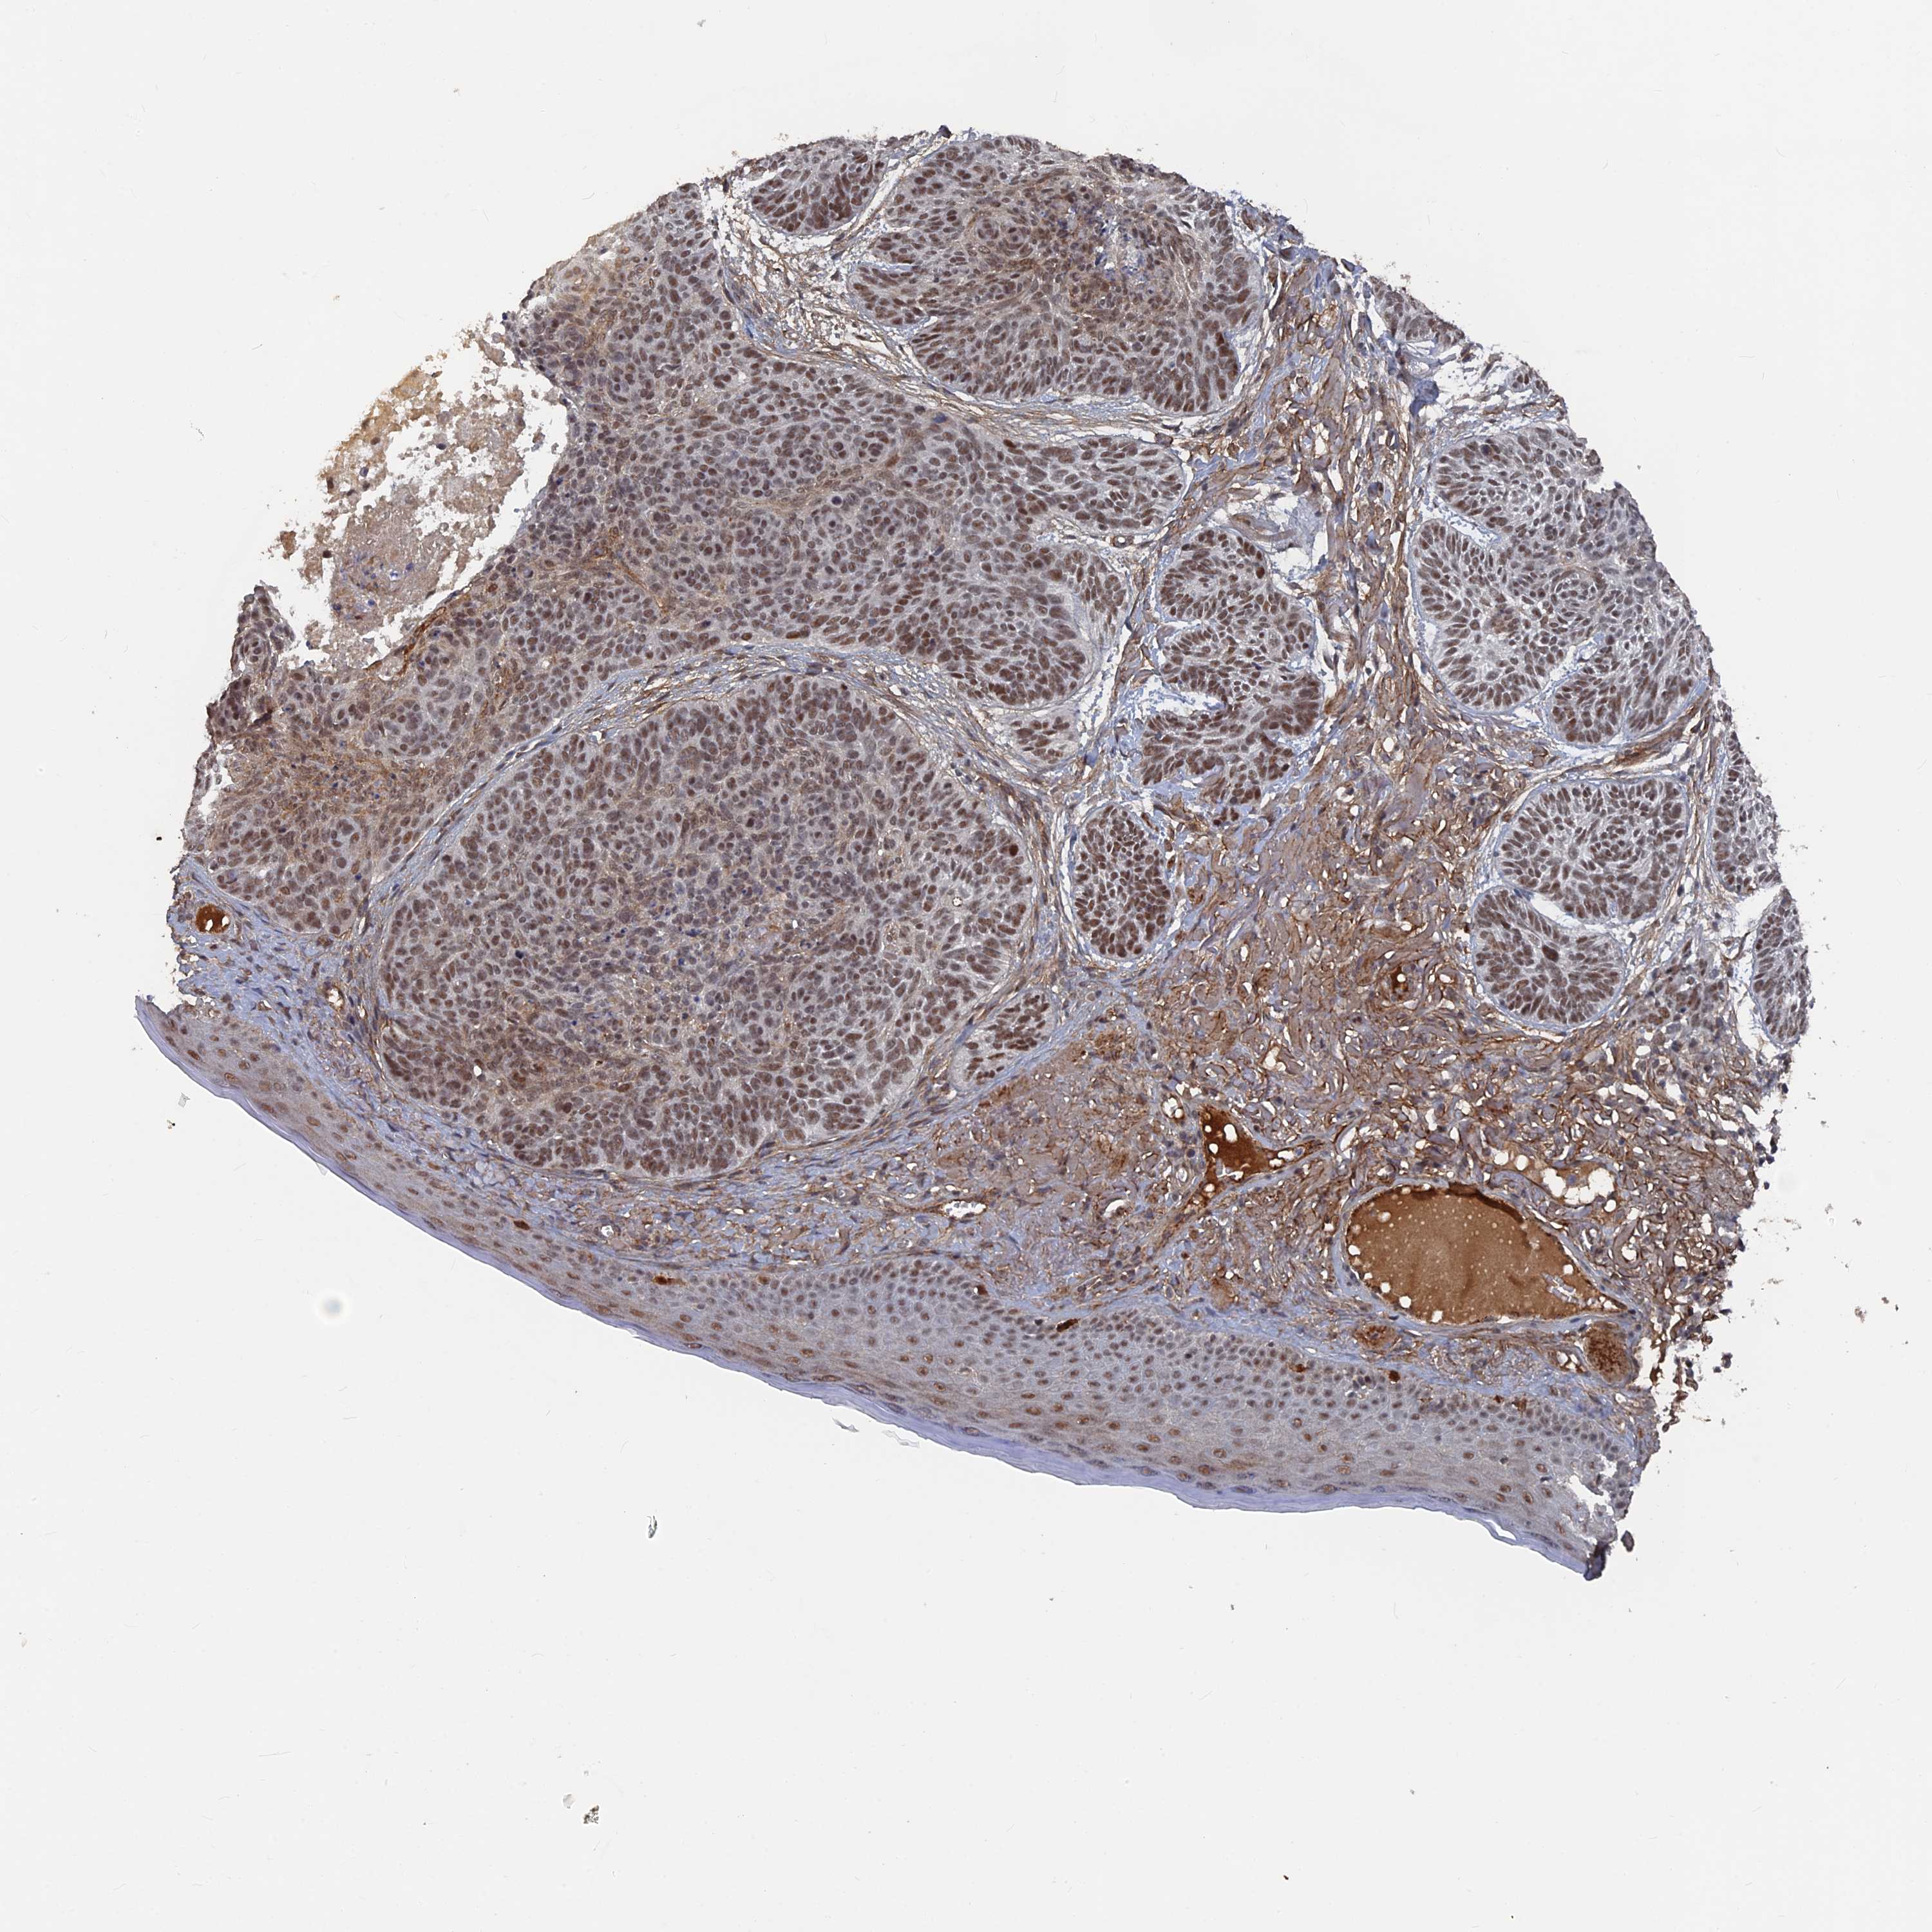

Basal cell and squamous cell cancer

SKIN CANCER - Protein expressioni

A mouse-over function shows sample information and annotation data. Click on an image to view it in a full screen mode. Samples can be filtered based on level of antibody staining by selecting one or several of the following categories: high, medium, low and not detected. The assay and annotation is described here.

Each image is clickable and will lead to virtual microscopy that enables deeper exploration of all samples and also displays staining intensity scores, fraction scores and subcellular localization as well as patient and tissue information for each sample.

Antibody HPA042212

Antibody HPA042456

Basal cell carcinoma